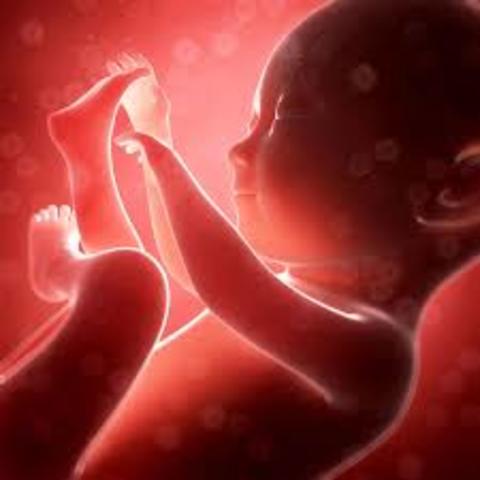

• period of fetus

period of fetus

week 9, the fetus is an inch long. The size of a grape. Baby's heart finishes dividing into four chambers, also teeth star developing. Eyes are formed and positioned to rapid weigh gain.

• during the end of the fetus period

during the end of the fetus period

week 9 to birth, the fetus continuous to grow, legs,head,fingers etc. At 10 weeks it starts to swallow and kick. Week 11 its almost fully formed. Week 12 baby starts to open and close its fingers. Mouth will start sucking movements. Intestine will move into abdomen cavity. Week 13 first trimester ends finger prints star to form. It is almost 3 inches long.